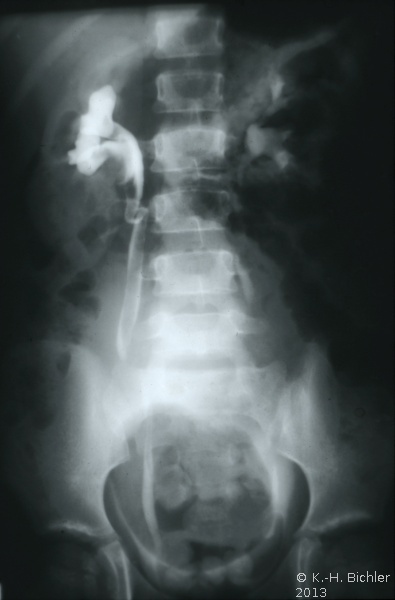

Die abdominale Sonographie bzw. die Computertomographie haben die Ausscheidungsurographie als die bildgebende Untersuchungstechnik bei Patienten mit Oberbauchtumor, z.B. Wilmstumor, verdrängt. Einige Ausscheidungsurographien von Kindern mit Wilmstumoren aus unserer Sammlung aus den 70er Jahren des vergangenen Jahrhunderts sind aus didaktischen Gründen hier wiedergegeben. Die Bilder zeigen instruktiv die Größe und Verdrängung durch den Tumor (

4 Abbildungen HG1).